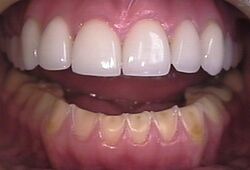

The erosion on the lower teeth was caused by bulimia. For comparison, the upper teeth were restored with porcelain veneers.[13]

Loss of enamel (acid erosion) from the inside of the upper front teeth as a result of bulimia